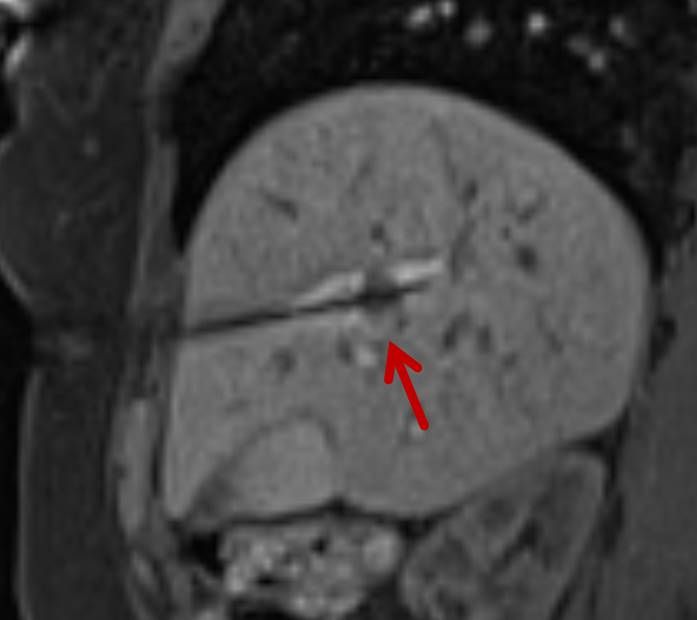

Präoperative Tumormarkierung

Eine Voraussetzung für die vollständige chirurgische Entfernung von Knochen- und Weichteiltumoren ist die präzise Erkennung der Tumorausdehnung und der Tumorgrenzen. Mit der Kernspintomographie (MRT) kann das Tumorgewebe exzellent von gesundem Gewebe abgegrenzt werden und somit die Ausdehnung vor der Operation bestimmt werden. Nach der kernspintomographischen Bestimmung der Tumorausdehnung werden unter kontinuierlicher MRT-Bildgebung die Grenzen des Tumors markiert. Die Marker werden mit einer Nadel ins angrenzende gesunde Gewebe eingebracht. Die Markierung kann am Tage vor der Operation durchgeführt werden. Alternativ ist die Tumormarkierung auch mit anderen bildgebenden Verfahren möglich, z.B. mit der Computertomographie oder dem Ultraschall.

Abbildung: Bei diesem Patienten wurde ein im Röntgen nur schlecht sichtbarer Knochentumor vor der Operation unter MRT-Kontrolle mit kleinen röntgendichten Spiralen („Coils“) markiert. Damit hat der Operateur eine optimale Darstellung des Tumorbereichs bzw. der Tumorgrenzen und kann gezielter, schonender und effektiver operieren.